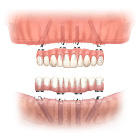

利用4-6顆植體及類似造橋的力學設計原理,將力量平均分配,使得傳統需要8-10顆植體才能支持的整排假牙,現在只須4-6顆植體即可達成。而且手術時間短,復原快速,如植體穩定性高,幾天之內患者就能恢復正常咀嚼。

圖3